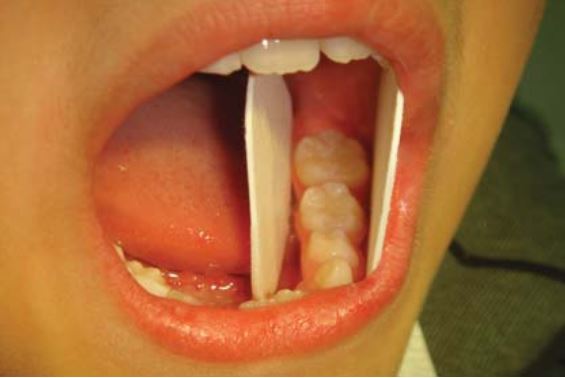

Có thể sử dụng một tấm chặn (dri – angle) để banh má khi trám các răng sau. Khi trám những răng cối sữa hàm dưới thì sử dụng thêm tấm chặn thứ 2 để banh lưỡi (H1.7).